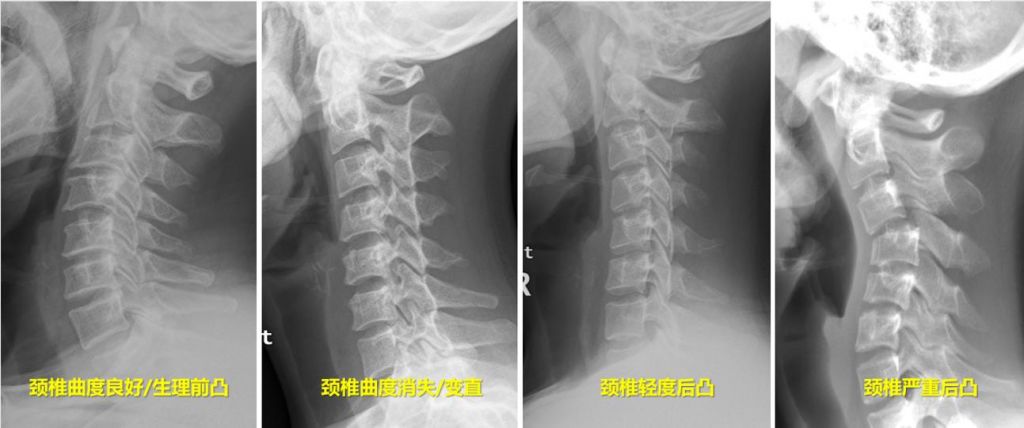

颈椎位于头以下胸椎以上的部位颈椎共有七个组成,除第一颈椎和第二颈椎外,其他颈椎之间都夹有一个椎间盘,加上第七颈椎和第一胸椎之间的椎。